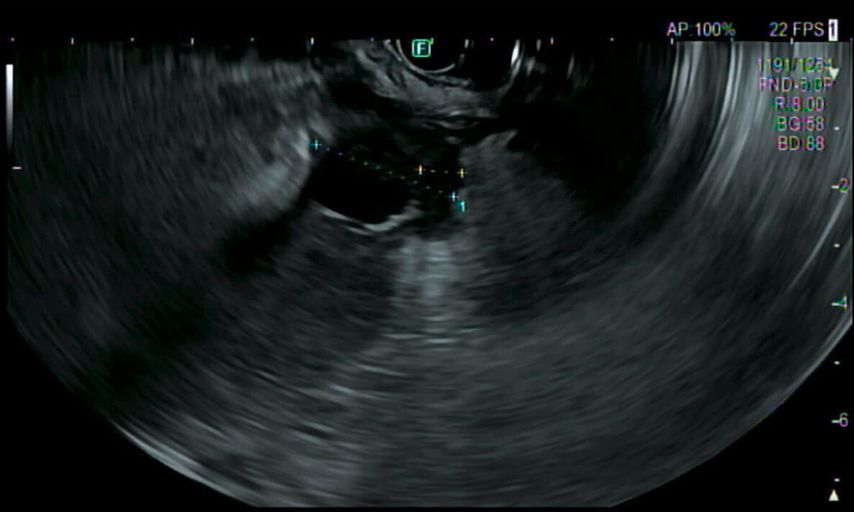

Eine Gastroskopie unter Intubationsnarkose wird angeschlossen (Abb.2). Gastroskopisch ist der Magen leer, die Schleimhaut adäquat durchblutet, ohne Ulzerationen oder malignomsuspekte Areale. Die einzige Auffälligkeit: Der Magen entfaltet sich nicht gänzlich, und zwar aufgrund einer submukös liegenden, verdrängenden Raumforderung im Bereich der Magenvorderwand. Aufgrund der Raumforderung kann der Pylorus nicht eingesehen werden.